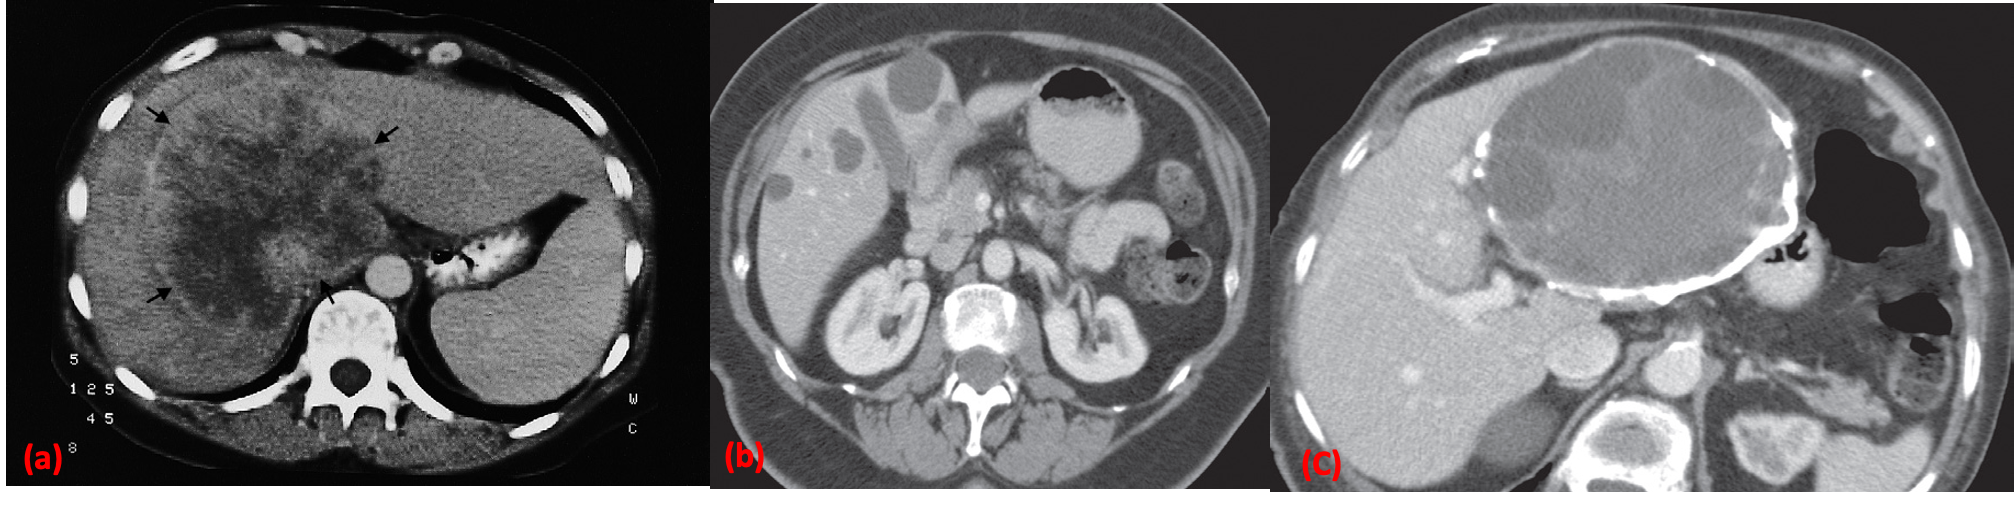

(a) CT scan of hepatoma showing a large mass of variable density (arrows). CT scan of liver cysts.

(b) Simple cysts. CT shows several well-defined, low attenuation lesions of near water density. Note their density is equivalent to the bile in the gall bladder.

(c) Complex cyst. CT scan showing a multilocular hydatid cyst with calcification in its wall.